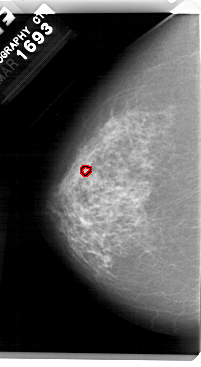

A_1480_1.RIGHT_MLO

RIGHT_MLO LINES 5491 PIXELS_PER_LINE 2986 BITS_PER_PIXEL 12 RESOLUTION 43.5 NON_OVERLAY

FILE: A_1480_1.LEFT_MLO.OVERLAY

TOTAL_ABNORMALITIES 1

ABNORMALITY 1

LESION_TYPE CALCIFICATION TYPE PLEOMORPHIC DISTRIBUTION CLUSTERED

ASSESSMENT 4

SUBTLETY 1

PATHOLOGY BENIGN

TOTAL_OUTLINES 1

BOUNDARY